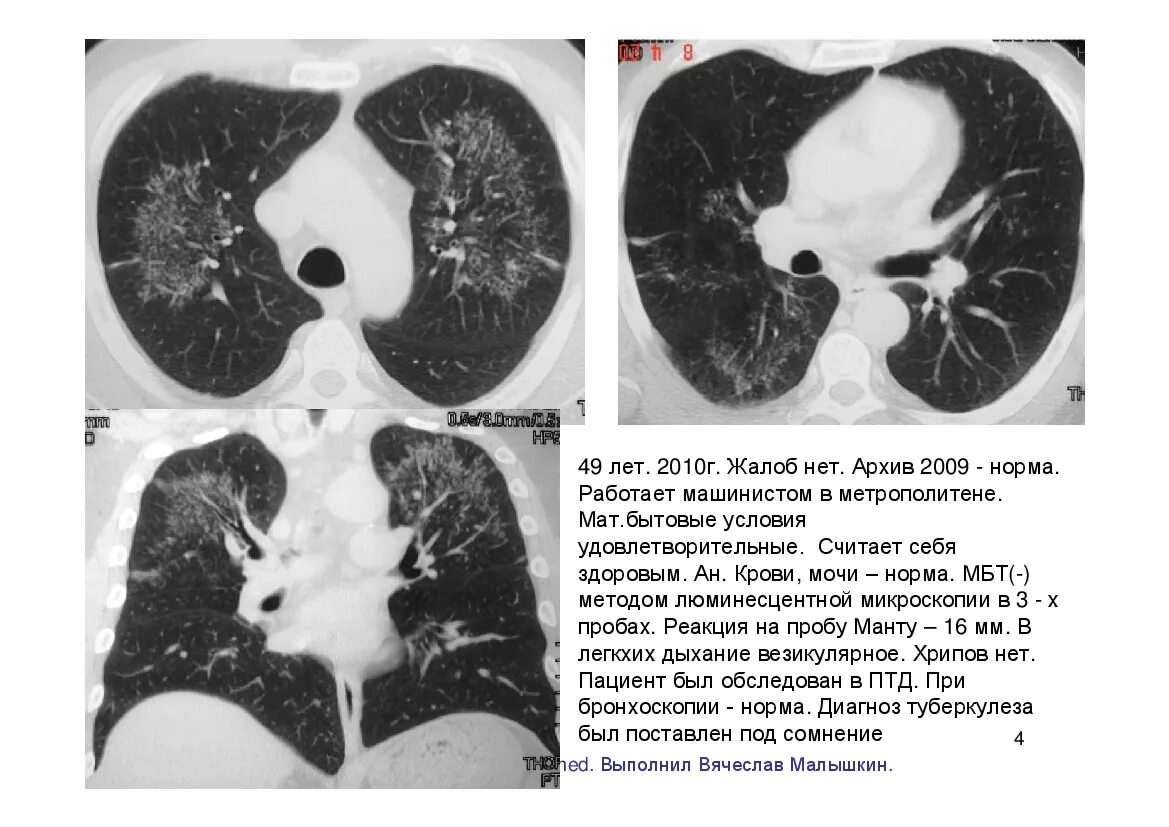

Мозаичная перфузия